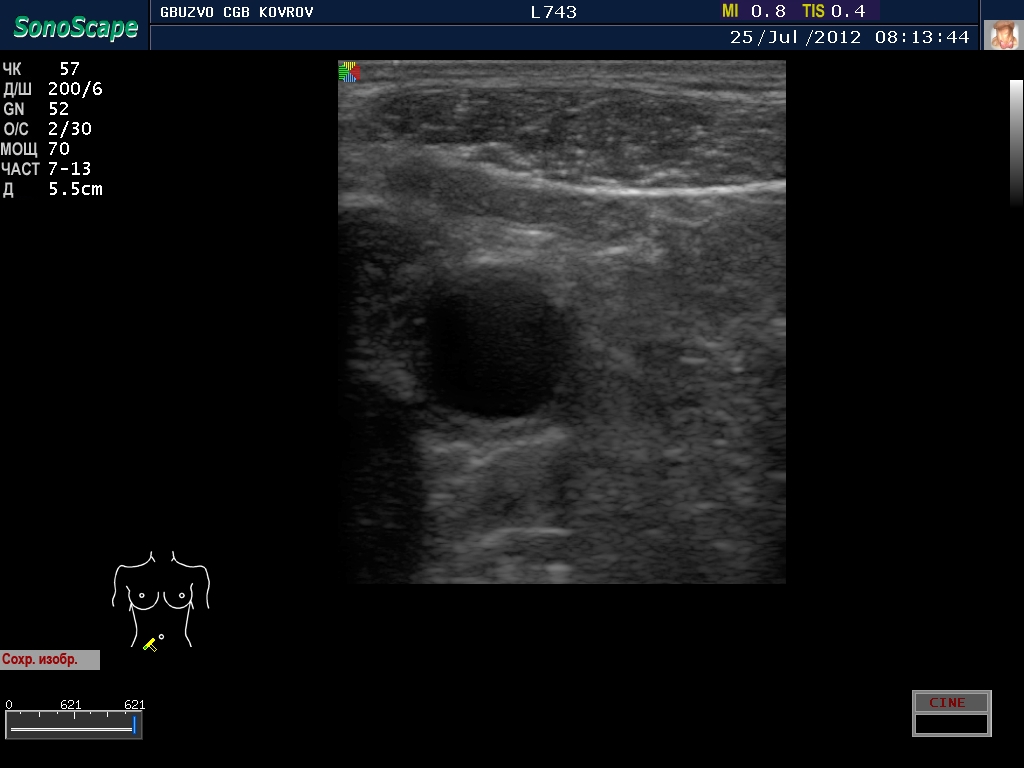

Пациент с жалобами на боли в животе...

полечили два дня в гастроэнтерологии...состояние ухудшилось, узи контроль----->

Что это такое? Кишка?

ну, скажем так, часть кишечника :D

поподробнее? :shock: бодимаркер находится в правой подвсздошной области, я бы подумал про аппендикс 8-)